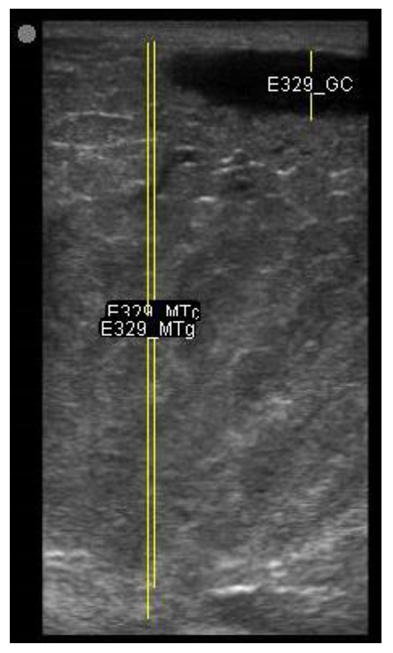

The image processing was undertaken using ImageJ software [28] as used by Abràmoff et al. [29]. The scales between pixels and millimetres were calculated based on the number of pixels, the scanning depth (mm), and the transducer width (mm) (Figure 4). This method relies on the ability of the operator to interpret and identify lines on the images. To standardize the assessment compartment depth, drawing templates were created for each time point as used by Molenaar et al. [30] and included four representative images from four different yearling ewes with and without the lines drawn for each compartment (Appendix A). The total depth of mammary gland conservative (MTc) was the smallest likely demarcation (abdominal wall) of the mammary gland (Figure 5a), and total depth of the mammary gland generous (MTg) was the largest likely demarcation of the mammary gland visible on the image [30] (Figure 5a). The MTc, MTg, fat pad (FP), parenchyma (PAR), and gland cistern (GC) depths were estimated at the deepest point for each sub-compartment, excluding the skin layers, using the straight tracer (Figure 5a) and were expressed in millimetres.

Figure 5.

(a) Demonstration of delimitations of the mammary total depth conservative (MTc) and generous (MTg), mammary gland cistern (GC), parenchyma (PAR) and the fat pad (FP) and (b) Demonstration of randomly positioning of regions of interest (1, 2, 3) in the parenchyma.